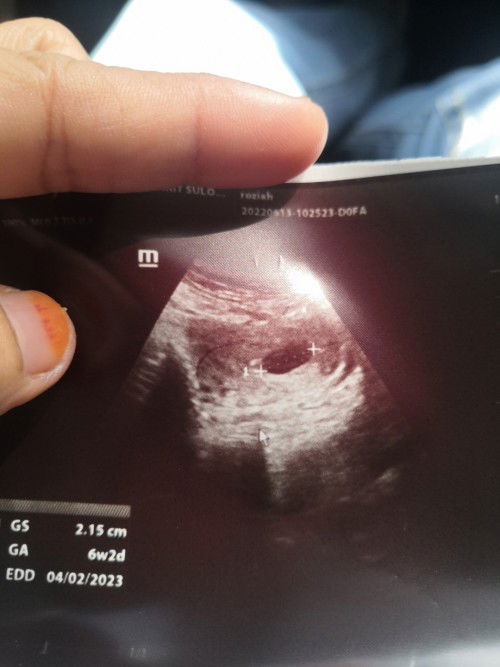

eh sama pulak tarikh edd kita. hihi kalau ikut tarikh last period, dah 9w. tapi sebab period xteratur dan kita tatau bila persenyawaan jadi, bila scan jadi 6w juga.

Baca lagiSama sis.. Saya ikut tarikh period dah 9 week.. Bila scan size kantung 6week..period ontime takda apa bleeding.. Byk baca persenyawaan lambat... Jdi tabahkan hati sementara nk tunggu next scan.. Moga ada berita gembira❤️

sama sy sis..ikut kiraan dr tarikh lmp 6 week 4 days..tapi scan 4 weeks 6 days..ape pun kne tgu repeat scan 2 mgu lg..moga khabar gembira utk kita 😉

Sama mcm sy . Ikutkan dah 7weeks . Tapi bila scan doc ukur kantung rupanya baru 6w. Persenyawaan lambat . Dan dr kata its normal awk 🥰

sbb kita xtau prsenyawaan tu bila. mcm sy 6 weeks bru nampak kantung. 9 weeks bru nampak janin n degupan jantung.. sis tunggu lagi 2 3 minggu inshaAllah nampak janin dan insaAllah ada degupan jantung.. lain org lain bdn. ada yg cpt nampak.. ada yg lmbt.. kalau scan pun normal xsilap sy kalau ada yg xsama weeks dgn first last period kita. apa2 pun kiraan tu, refer pada dr punya pandangan . kalau dr kata normal kiraan tu,normal la tu ❤️